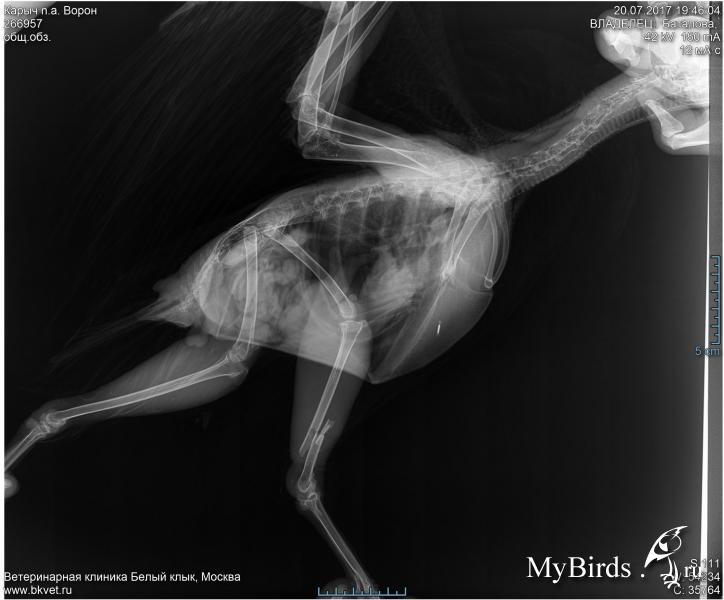

Ворон. Оскольчатый перелом голени.

В Москве 16 июля был подобран ворон. К врачу его отвезли только 20 июля.

Итак. Побывал на приёме у Томашевского.

На лапе что-то вроде лангетки. По тому, что лапа выглядит короче другой, подозреваю, что кости зафиксировали как они есть на рентгене. Надеюсь, что это не так, но пока добраться до врача не могу, не на кого оставить сороку. Да и времени уже прошло много для того, чтоб просто исправить было.

На сломанной лапе потеряна чувствительность, пальчики не реагируют, как ватные. На основании этого было заявлено, что чувствительность не восстановится и предложили подумать по поводу усыпления птицы.

Причём не было дано никакого объяснения почему потеряна чувствительность. Только категоричное заявление о невозможности восстановления без операции, но операция де слишком рискованна: может не дать результата и можно вообще потерять лапу.

Как вариант, если подтвердиться слишком высокий риск операции, буду пытаться восстановить лапу исходя из того, что есть. Лучше хромая птица, чем без ноги или мёртвая. Посему интересует, что может быть причиной потери чувствительности. Я по рентгену, кроме очевидного перелома, ничего не вижу, опыта не хватает.

На лапе 2 ложных сустава. Почему Томашевский не назначил кальций полная загадка. Через 10 дней явка, там уже будем смотреть, что делать дальше. Перелом был открытый, рана зажила хорошо.